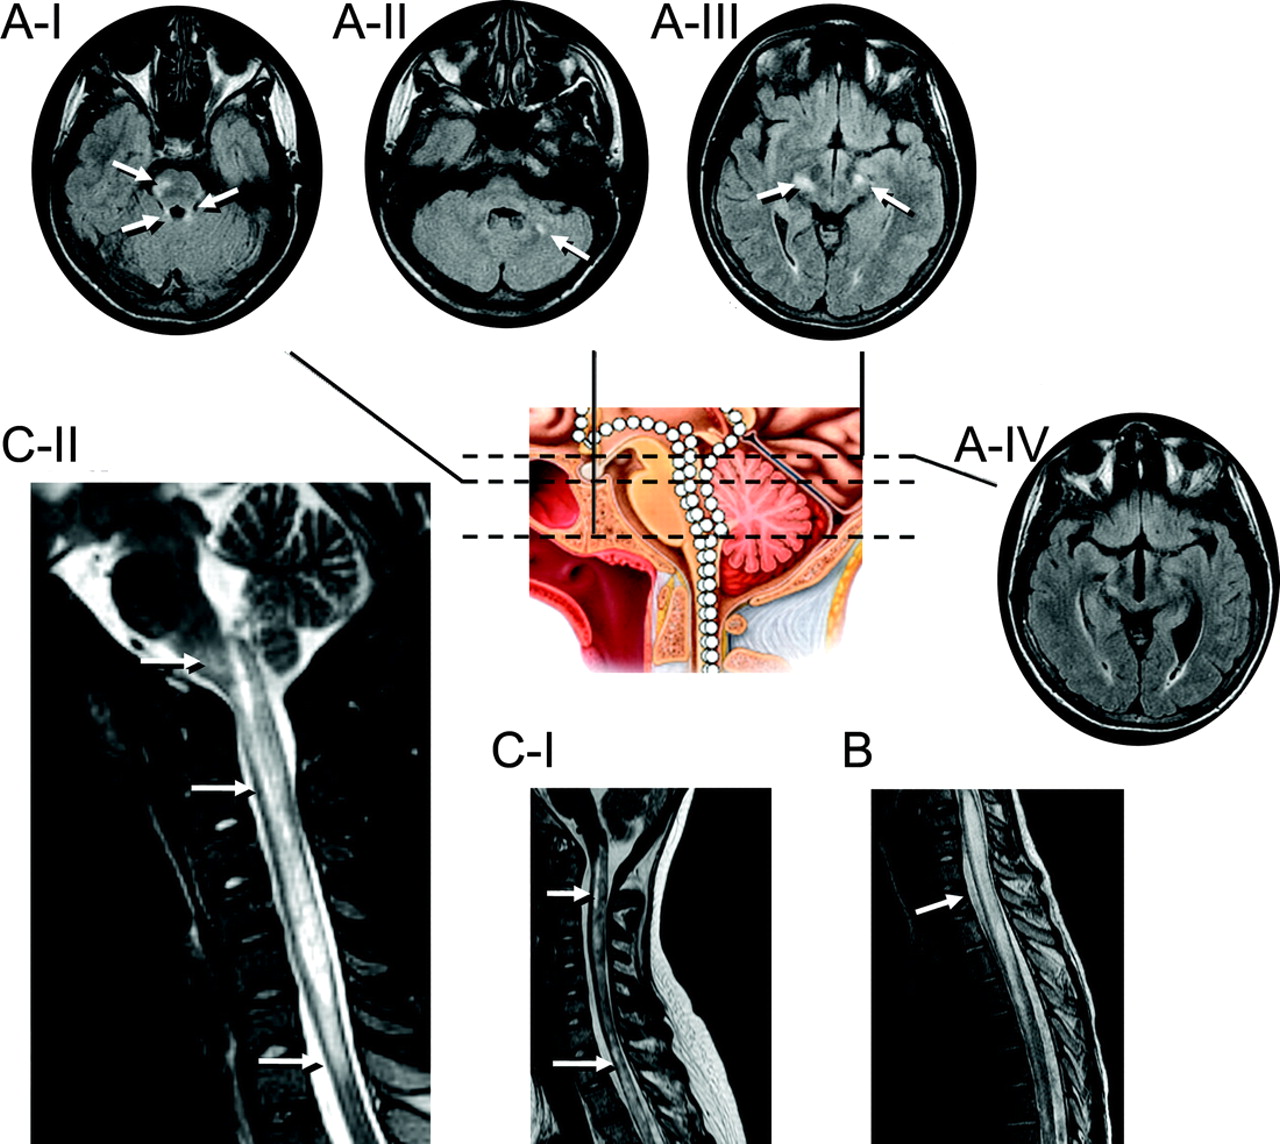

图3七个孩子代表MRI异常显示出脑干的频谱,周围,peri-IVth心室和脊髓参与地区已知高度表达aquaporin-4

白色的箭头表示异常液体衰减反转恢复或T2信号。冲黑色线条代表解剖水平关系图。(一)病人5(17岁的女孩;另请参阅图1中,E通过我)两国在上级小脑的病变总花梗(ⅰ),在小脑白质病变(A-II)和双边病变内部胶囊(A-III)。四年后病人出现症状性阻塞性脑积水(iv,也看到图1E-II;内囊损伤已经解决)。(B)病人8(11岁女孩)纵向广泛T2在中央脊髓异常通常是发现在成年neuromyelitis视(在本例中11椎段)。(我)病人9(17岁的女孩出现棘手的呕吐,四肢瘫痪,补剂肢体痉挛)和(C-II)病人11(17岁的女孩出现棘手的呕吐)纵向跨越脑干损伤和中央颈,胸线。